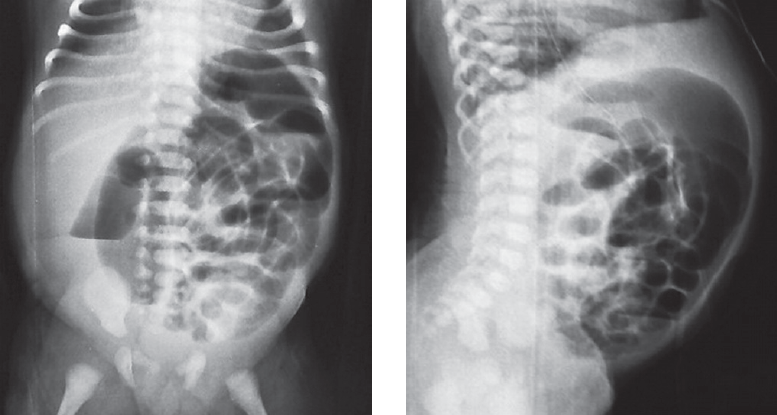

Доношенный ребенок поступил в возрасте 3 сут жизни с клиникой кишечной непроходимости: срыгивания с примесью желчи, вздутие живота, отсутствие стула. Осмотр промежности ребенка не вызвал вопросов у хирурга, по клинико-рентгенологическим данным была заподозрена болезнь Гиршпрунга. Ежедневно выполнялись очистительные клизмы. Контрастное исследование толстой кишки произведено в возрасте 14 дней жизни. По данным ирригографии выявлено резкое расширение дистального отдела сигмовидной кишки (рис. 4).

Рис. 4. Ирригография

Fig. 4. Contrast enema

Диагноз ректосигмоидной формы болезни Гиршпрунга казался очевидным и были поставлены показания к оперативному лечению. На операционном столе при попытке опорожнения кишечника выявлено затруднение при заведении газоотводной трубки. Заподозрен стеноз ануса и прямой кишки. Выполнено калибровочное бужирование, на основании которого диагноз был подтвержден. Ребенок снят с операционного стола. Болезнь Гиршпрунга была исключена. Пролечен консервативно систематическим бужированием.

Ирригография является обязательным исследованием у всех детей с подозрением на болезнь Гиршпрунга [2]. Чувствительность и специфичность метода по литературным данным достигает 70 и 80 % соответственно. Хорошо известно, что диагностическая значимость ирригографии в определении переходной зоны у новорожденных с болезнью Гиршпрунга меньше, чем у детей более старшего возраста (65 против 75 %) [3]. I.R. Diamond et al [4]. описали возможные предрасполагающие факторы получения ложноположительных результатов при выполнении контрастного исследования у пациентов с болезнью Гиршпрунга, одним из них является возраст ребенка. У детей в возрасте 30 сут жизни было больше ложноположительных результатов, чем у пациентов младшего возраста. Срок выполнения рентгенологического обследования зависит от нескольких факторов, главным из которых является эффективность опорожнения толстой кишки. Обследование целесообразно выполнять не сразу после поступления новорожденного в стационар, а отсроченно, после купирования явлений Гиршпрунг-ассоциированного энтероколита, чтобы исключить сужение кишки, связанное с ее спазмом на фоне воспалительных явлений. Конечно, это не касается ситуаций, когда есть клиника некупирующейся кишечной непроходимости, либо признаки «токсического» мегаколона. В этих случаях ирригография обязательно проводится непосредственно при поступлении ребенка в стационар. В остальных случаях, когда декомпрессия кишечника эффективна, исследование может быть отложено на несколько дней, до полной стабилизации состояния и нормализации клинико-лабораторных показателей. Контрастирование толстой кишки у детей с клиникой низкой кишечной непроходимости носит не только диагностический, но и лечебный характер, особенно при синдромах мекониальной пробки и суженной левой половины толстой кишки, которые могут быть причиной для постановки ложноположительного диагноза болезни Гиршпрунга. Надо отметить, что ирригография, выполненная в первые дни жизни ребенка сразу после появления клиники непроходимости, и отсроченное исследование могут отличаться друг от друга. На представленных рентгенограммах одного и того же ребенка с разницей в две недели видны существенные различия (рис. 8, а, b). Если на первичной ирригограмме можно оценить лишь правильность расположения толстой кишки и наличие в ней большого количества содержимого, то при исследовании через 2 недели видны четкие признаки ректосигмоидной формы болезни Гиршпрунга с наличием зоны сужения и воронкообразным супрастенотическим расширением.

Рис. 8. Ирригография; а — вторые сутки жизни; b — две недели жизни

Fig. 8. Contrast enema. а – second day of life; b – two weeks of life